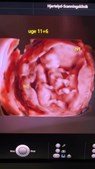

Så er der nyt fra Hjertelyd - scanningsklinik for gravide